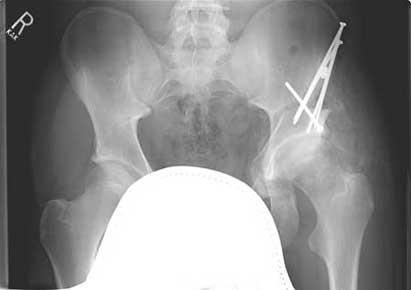

Heterotopic ossification of the left hip developed a few months after periacetabular osteotomy

Heterotopic ossification of the left hip developed a few months after periacetabular osteotomy.